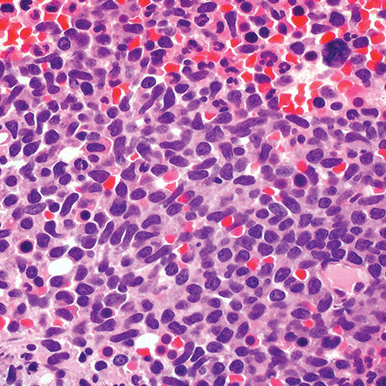

Bone marrow

Core biopsy showing diffuse infiltrate by BPDCN (H&E stain, x600).11

H&E, hematoxylin and eosin.

Main morphologic features of BPDCN biopsy

• Diffuse, monomorphic infiltrate1

• Medium-sized blast cells with irregular nuclei1

• Fine chromatin1

• At least 1 small nucleolus1

• Malignant BPDCN cells do not typically infiltrate the epidermis4